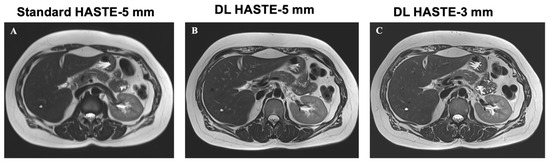

3.5. Lesion Detection